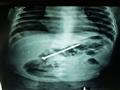

أعلن الدكتور أحمد الرفاعي، مدير مستشفى الأطفال بجامعة المنصورة، اليوم الخميس، إجراء فريق جراحى بوحدة الجهاز الهضمي عملية جراحية لاستخراج مسمار بطول 6 سم، باستخدام المنظار بدون أي جرح أو مضاعفات أو تدخل جراحى من بطن طفل عمره 9 شهور.

وذكر بيان لجامعة المنصورة، أن فريق طبي ضم الدكتور محمد عز الرجال، والدكتور أحمد مجاهد، استاذ طب الاطفال والجهاز الهضمي، والدكتور محمد مرسي، أخصائي اطفال وجهاز هضمى، والدكتور منصور صقر، أخصائي أطفال نجح فى استخراج المسمار دون جراحة.

وقال الدكتور محمد عز الرجال، أن الطفل كان يلهو مع شقيقه البالغ ٣سنوات فى عدم وجود الأم بعدها أخبرالطفل الكبير والدته أن أخيه ابتلع مسمار.

وأضاف:"الأم حاولت على مدار 6 أيام استخراج المسمار طبيًا، حتى جاءت مستشفى الاطفال وعرضت الحالة على الفريق الطبى لإجراء الاشعة لتحديد مكان المسمار.

واوضح عزالراجل أن العمليه انتهت بسلام دون مضاعفات وغادر الطفل المستشفى فى نفس اليوم.